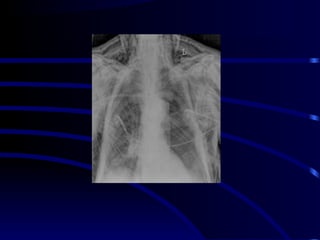

At the bedside, chest radiography remains the reference for lung

imaging in critically ill patients. However, radiographical images are

often of limited quality

• Movements of the chest wall

• Film cassette posterior to the

thorax

• X-ray beam originating

anteriorly, at a shorter distance

than recommended and not

tangential to the diaphragmatic

cupola .